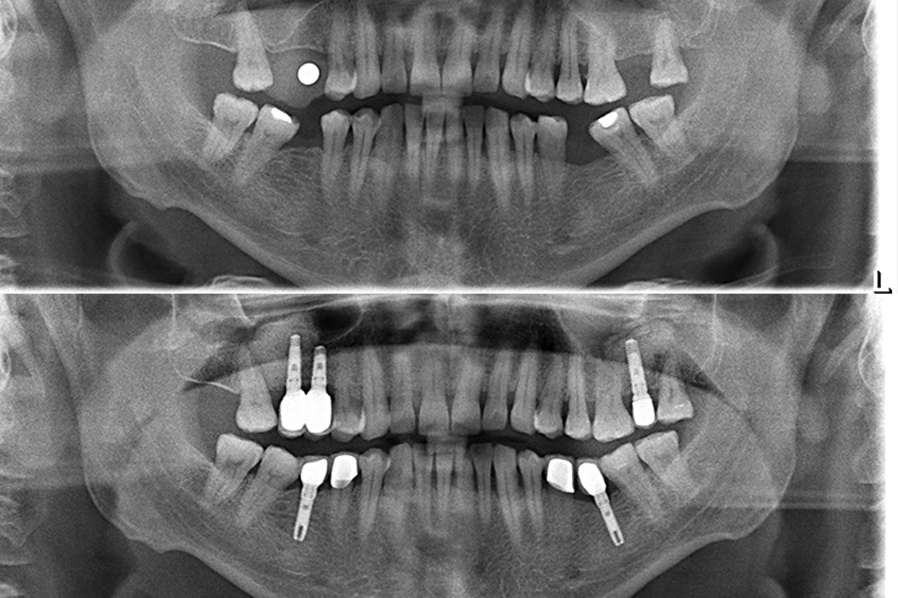

Birden fazla sayıda olan diş eksikliklerini, eksik diş sayısı kadar ya da daha az sayıda implant ile tedavi etmek mümkündür. Bu yöntem sayesinde hareketli protez yerine sabit protez kullanmak mümkün olabilir. Sabit protezin hareketli proteze göre pek çok üstün özellikleri vardır. Hasta sabit proteze daha çabuk uyum sağlar, sabit protezde hareketli proteze göre daha etkin bir çiğneme ve estetik sonuç elde edilir.